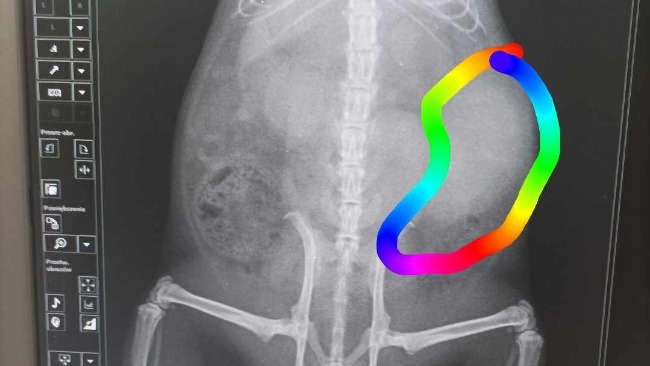

Jestem Ania i los zwierząt nie jest mi obojętny.Chcę uratować od śmierci Bellę,ale niestety nie ma dużo czasu. Jest to szczurka którą opiekuje się młody chłopak. Antek ma Bellę i Telmę, która jest po ciężkiej operacji usunięcia guza(niestety jest to guz złośliwy) i jest ona trakcie leczenia. Telma ma wodę w płucach oraz ich obrzęk,wadę serca(kardiomiopatie przyrostową) ,zaburzenia hormonalne i problemy z wątrobą. Co do drugiej szczurki to Bella zachorowała nagle , a pierwszym jej objawem był niepokój,krążenie w okół własnej osi i gryzienie ogonka z bólu.Na pierwszej wizycie która miała miejsce 3.02.24 okazało się po badaniu USG, że ma guz jamy brzusznej przy śledzionie wielkości 3,5 cm .Jesli natychmiast nie z operujemy guza to szczurka umrze. Koszt operacji to 400 zł+ kolejne wizyty oraz leki na jakiś czas. Jest to naprawdę duża suma szczególnie dla tak młodego człowieka który dopiero co wszedł w dorosłe życie. Proszę Was o pomoc w uratowaniu Belli! Nie bądźmy obojętni, pomagajmy! Dobro wraca!